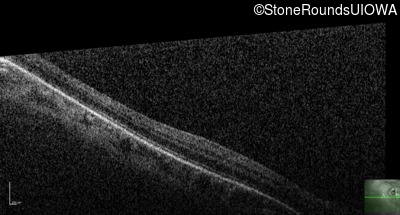

Optical Coherence Tomography - Right - 20/80

Exemplar / OCT Stack